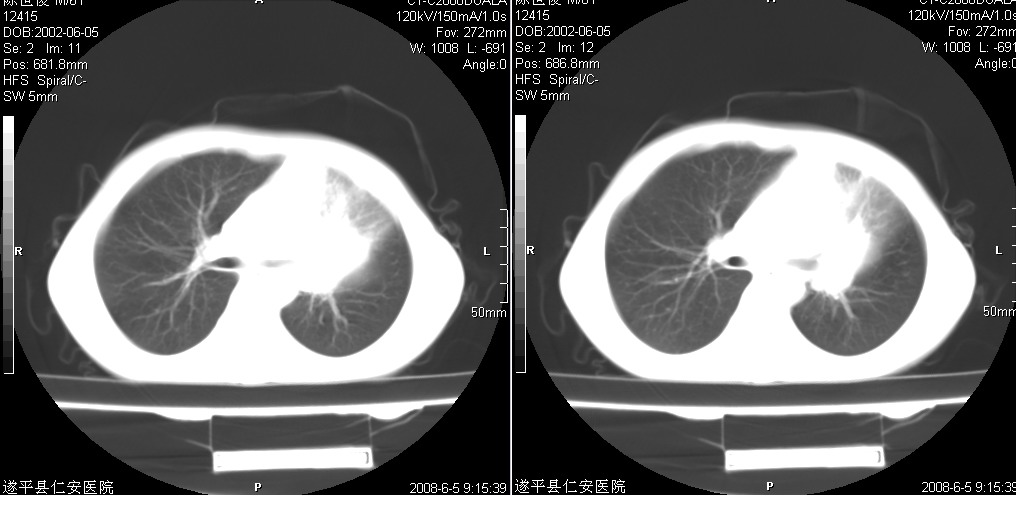

以下是引用xxhwh在2008-6-10 18:40:00的发言:[br]男,6岁,无规则发热一月余,体温在37.8——39度之间。一月前拍胸片示左上肺密度增高影,进行抗炎治疗8天,复查胸片未明显吸收。又改变抗菌素继续治疗半月,照胸片示病灶吸收不明显,行ct检查[br]征象:左上肺前段呈密实影,内可见支气管气像,远侧见絮状模糊影,中上纵隔左移。[br]意见:左上肺前段膨胀不全及感染,考虑为支气管异物或支气管内膜结核所致,[br]建议追问有无异物吸入史,行痰检及ppd检查